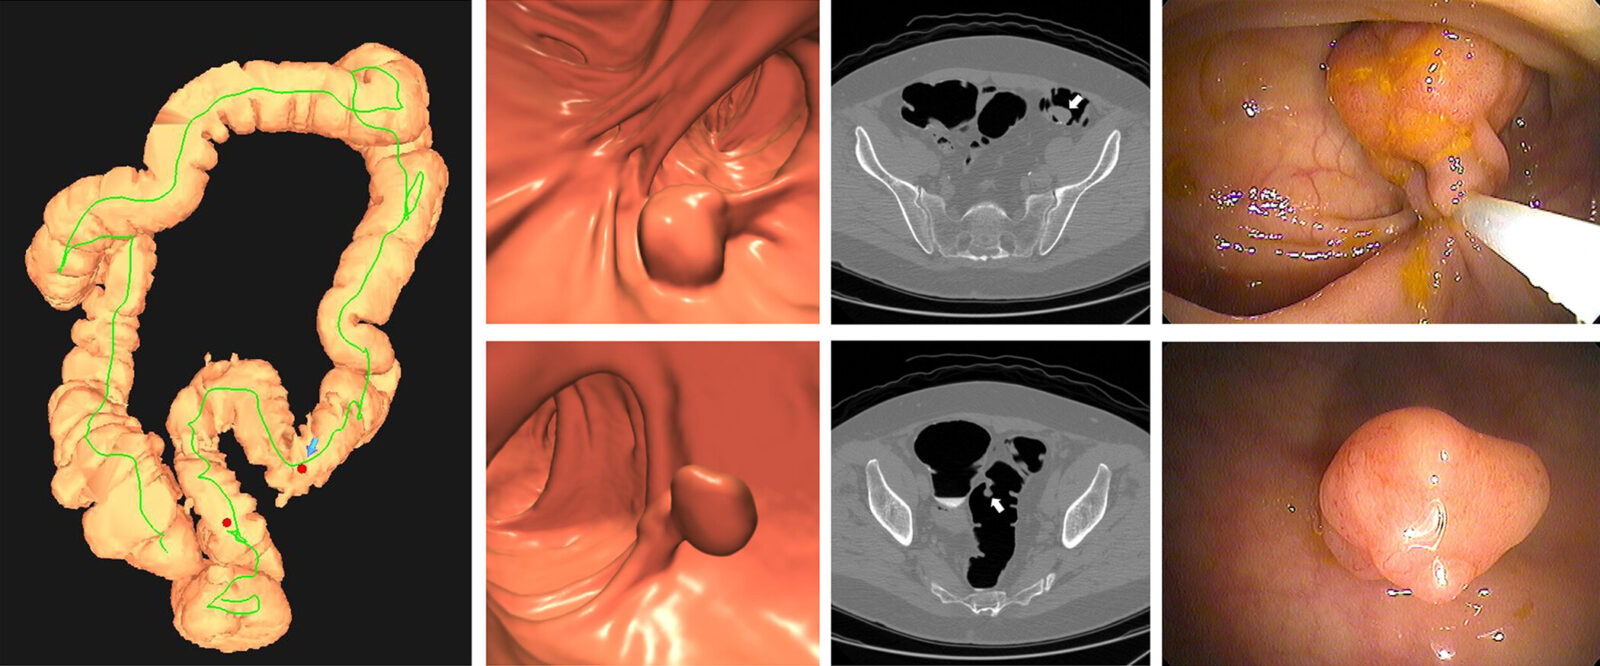

Unlike colonoscopy, there’s no risk of bleeding or perforating the colon associated with CTC. Instead of a scope, computed tomography scans are used to create 3D images of a patient’s colon from different angles. Patients are able to resume normal activities and even drive themselves home following the procedure. If polyps are detected, same-day GI Clinic services are available for polypectomies.

While stool testing is also a non-invasive screening method, CTC outperforms it in a crucial area: detecting precancerous polyps. By identifying and removing these types of polyps, patients can effectively prevent cancer that they may have developed later in life.